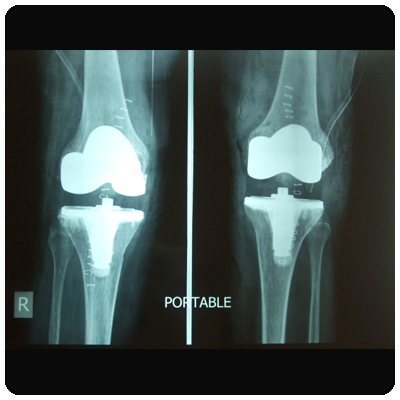

Inder Lal Bahri (Right Total Knee Replacement)

Name: Neeta Dey (Bi Lateral Knee Replacement)

Nemchand Jain : Bilateral Knee Replacement

SK Mehta : Bilateral Total Knee replacemnt